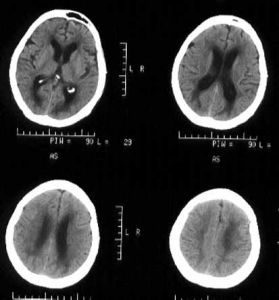

腦白質病合併腦萎縮的CT表現腦白質病的影像學檢測手段中,加權磁共振成像是首選檢查手段,是鑑別早期或輕微腦白質病與精神疾病的重要手段,而CT僅能顯示重度腦白質損害。

2、CT診斷

CT具有高密度解析度和空間解析度,平掃即可較清晰區分大腦半球和小腦半球的白質和灰質,增強CT掃描則可增加腦白質病灶的顯示能力。但是CT的軟組織對比解析度較低,顯示腦幹和小腦不佳。所以,CT不能完全顯示某些腦白質病灶、其定位和定性診斷能力均受限。

2、腦白質稀疏:好發於50歲以上者,常見於痴呆及腦血管患者。CT特徵表現為雙側腦白質對稱性低密度灶,或並發腦梗塞、腦出血及腦萎縮。